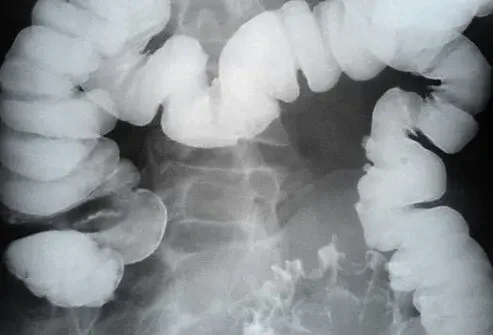

Un diverticolo è una sacca sporgente o un sacco che può formarsi sugli organi interni. In questa presentazione discuteremo di diverticoli del colon che sono sacche sporgenti che spingono verso l'esterno sulla parete del colon. La diverticola (plurale per diverticolo) può verificarsi ovunque nel colon ma più comunemente si forma vicino alla fine del colon sul lato sinistro (colon sigmoideo).

Quando un paziente ha diverticoli (sacche sporgenti) nel colon, questo è chiamato diverticolosi o malattia diverticolare.

Le diverticoli vengono diagnosticate mediante sigmoidoscopia o colonscopia che sono ambiti con telecamere usate per guardare all'interno del colon. AVERTICOLA può anche essere diagnosticata con una risonanza magnetica o una TAC dell'addome e del bacino. A volte viene utilizzata una radiografia del bario (clistere di bario). Durante una riacutizzazione acuta della diverticolite una TAC può essere utilizzata per diagnosticare l'entità dell'infezione.